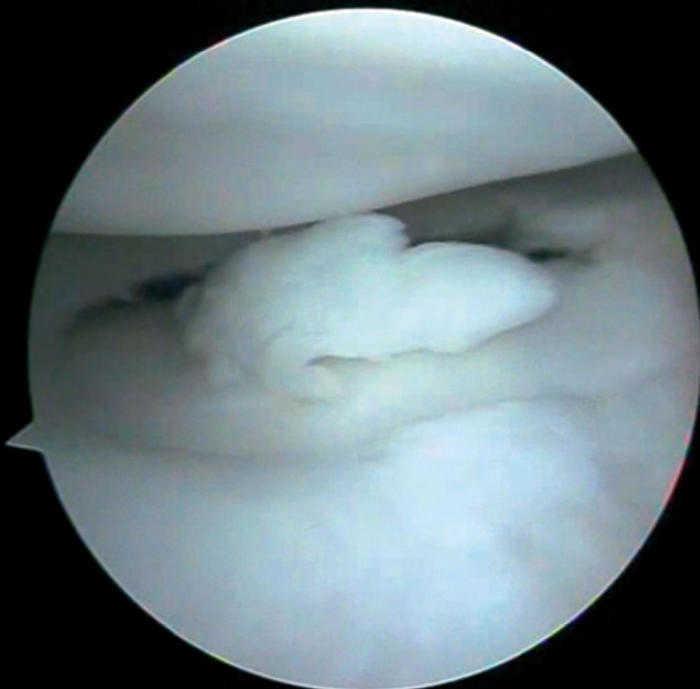

Figura 2 Artroscòpia. Cossos lliures articulars en recessió articular interna.

Es practica una artroscòpia, en la qual s'observen (figs. 2, 4, 6-8):

• Múltiples fragments condrals lliures de vores agudes, que s'identifiquen com recents, i de vores rodones que es cataloguen com antics.

• Lesió condral anfractuosa extensa, amb fragments inestables en cres-ta de la ròtula i en faceta externa, de grau III.

• Resta d'estructures intraarticulars íntegres.

• Es procedeix a l'exèresi dels cossos lliures i la regularització de la lesió condral seguida d'estabilització per vaporització.